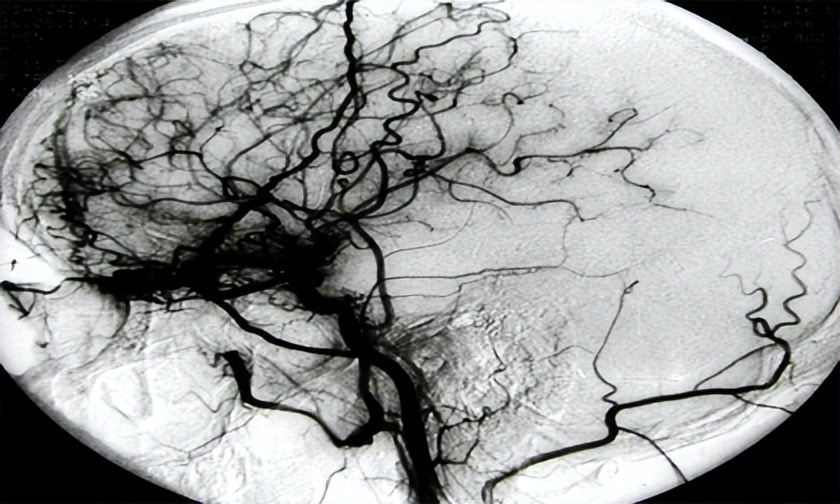

“烟雾病”是一种 脑血管疾病

而它梦幻名字的由来

只因在做脑血管造影时

会呈现许多密集成堆的小血管

形似烟雾而得名